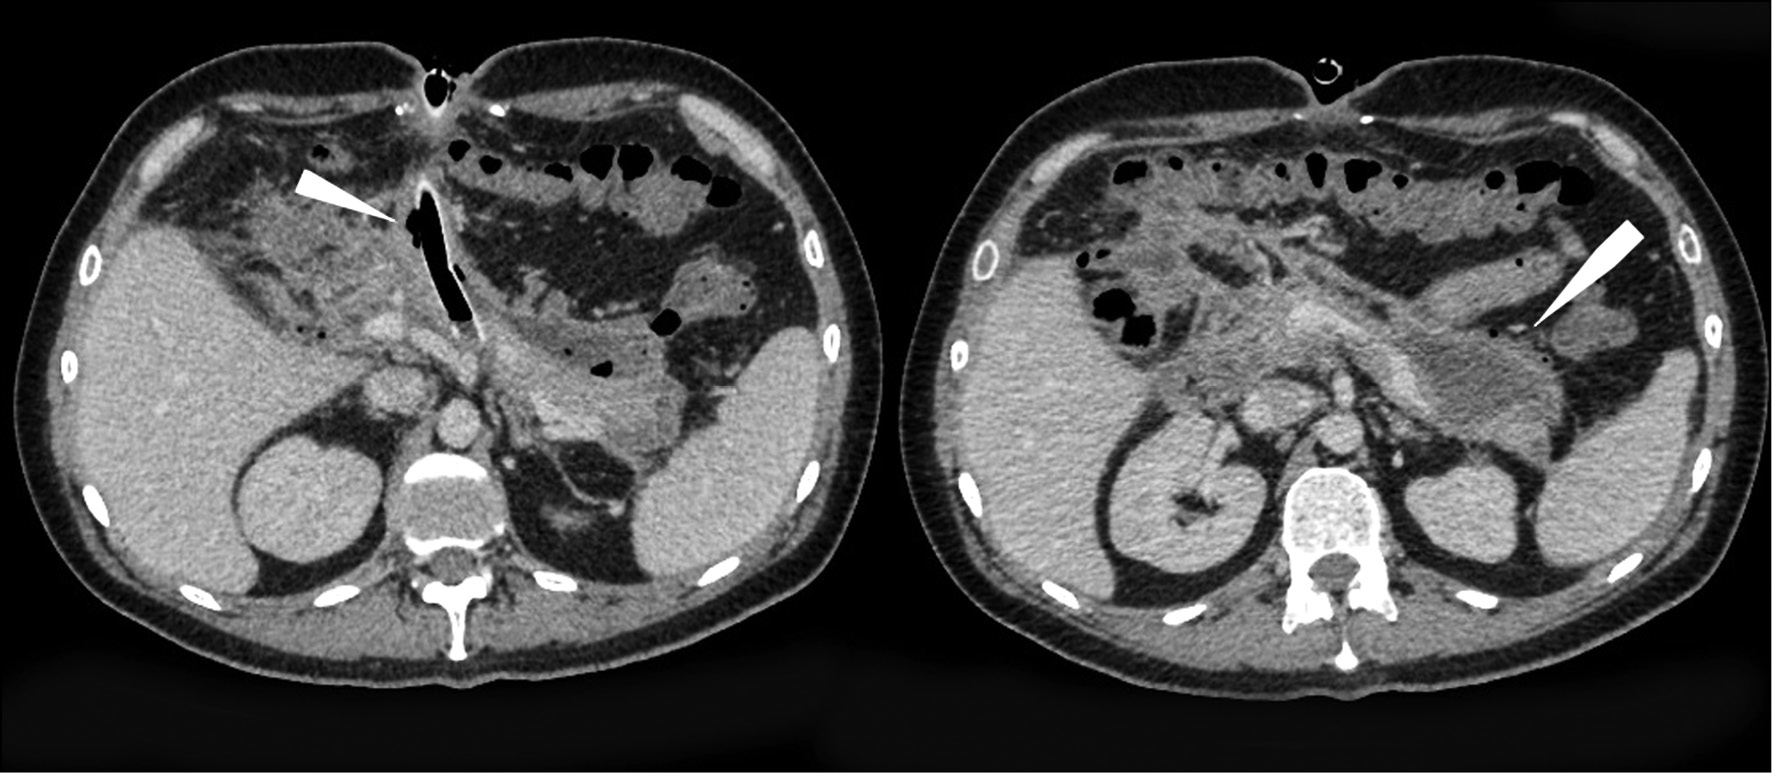

At the control AO CT scan (02/01; 02/02; 02/05/2018), the CT presentation showed no deterioration; the state of the pancreas and fluid accumulation along the gland contour in the area of the omental sac had changed; non-draining fluid accumulations in the retroperitoneal space were not detected (Fig. 3).

Fig. 3. Computed tomography of abdominal organs with intravenous contrast: infiltration and fluid accumulations in the peripancreatic adipose tissue, along the course of the amniotic fascia on the left, in the parenchyma of the head and body of the pancreas (arrows); drainage tube (zigzag arrow in the image on the left). In dynamics, the formation of a thin contrasting capsule along the course of the infiltration zone is noted.